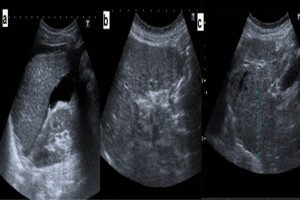

Diplomados en Ultrasonografía